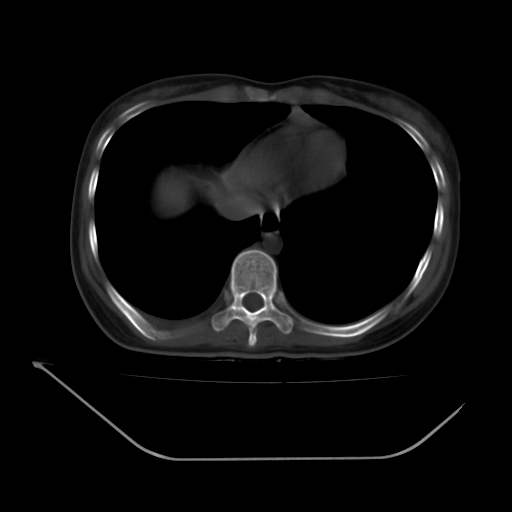

以下是引用liuyue在2008-7-19 13:02:00的发言:[br]1.肝右叶后下段及右肾挫裂伤伴腹腔积血。[br]2.右侧多发性肋骨骨折、横突骨折、右髂骨骨折伴周围软组织挫伤。[br]3.右侧腰大肌肿胀,并可见低密度影,如为气体,则肠道挫裂伤待除外。

以下是引用zhengfaming在2008-7-19 14:42:00的发言:[br]1.肝右叶后下段及右肾挫裂伤伴腹腔积血。脾脏挫裂伤待排[br]2.右侧多发性肋骨骨折、横突骨折、右髂骨骨折伴周围软组织挫伤。[br]3.右侧腰大肌肿胀,并可见低密度影,如为气体,则肠道挫裂伤待除外

以下是引用道哥在2008-7-19 16:52:00的发言:[br]肝右叶后下段及右肾挫裂伤、脾破裂伴腹腔积血。[br]2.双侧多发性肋骨骨折、横突骨折、右髂骨骨折伴周围软组织挫伤。[br]3.右侧腰大肌肿胀,并可见低密度影,如为气体,则肠道挫裂伤待除外。